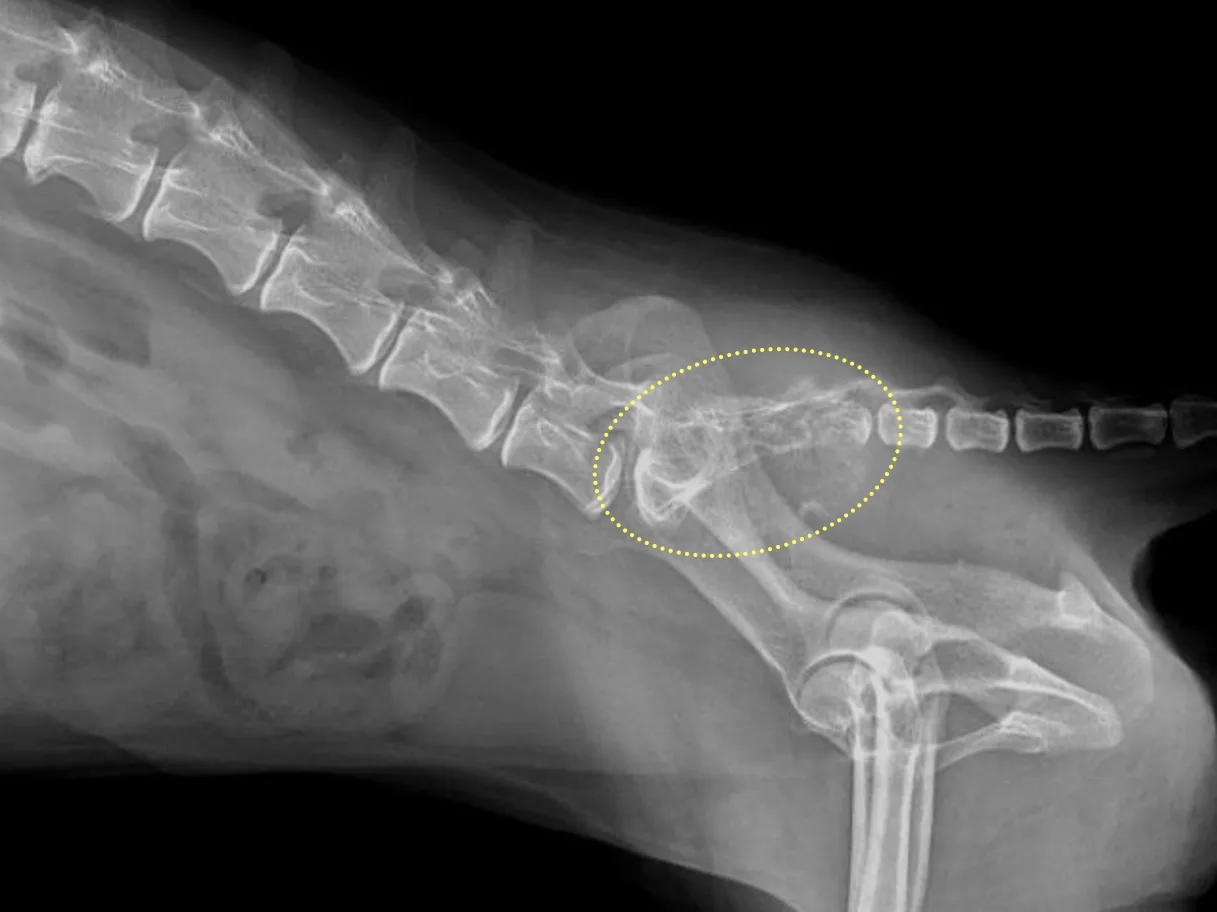

胸部/骨レントゲン検査

肺転移や骨転移の有無を評価します。

4、尿路閉塞が起こっている場合

・尿道閉塞:尿道ステント設置術、膀胱瘻チューブ設置術

・尿管閉塞:尿管ステント設置術、SUBシステム設置術